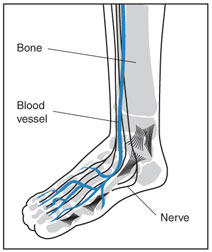

Peripheral neuropathy (nerve damage) and lower extremity ischemia (lack of blood flow) due to peripheral artery disease are the primary causes of diabetic foot ulcers.

Diabetic peripheral neuropathy is a precipitating factor in almost 90% of diabetic foot ulcers. Chronically high glucose (blood sugar) levels damage nerves, including the sensory, motor and autonomic nerves. Diabetic neuropathy also damages the immune system and impairs the body's ability to fight infection.

Sensory nerves enable people to feel pain, temperature, and other sensations. When sensory nerves of a diabetic person are damaged (sensory neuropathy), they may no longer be able to feel heat, cold, or pain in their feet. A cut or foot sore, a burn from hot water, or exposure to extreme cold might go completely unnoticed because of numbness and lack of sensation. The sore or exposed area may then become infected and not heal properly due to the body's impaired ability to fight infection.

Peripheral neuropathy also causes muscle weakness and loss of reflexes, especially at the ankle. This may change the way a person walks and lead to foot abnormalities and deformities such as bunions, hammertoes, and charcot foot. These play an important role in the pathway of diabetic foot ulcers since they contribute to abnormal pressures in the plantar area (heel and bottom) of the foot, predisposing it to ulceration.

Diabetes also damages blood vessels by causing inflammation and atherosclerosis, or hardening of the arteries. Narrowing of the arteries causes ischemia, a condition in which the blood circulation in the arteries is restricted and the availability of oxygen, glucose, and critical nutrients to tissues in the body is substantially reduced. When poor circulation affects the arteries of the feet and hands, it is called peripheral artery disease, or PAD. By restricting the supply of oxygenated, nutrient-rich blood to the site of the ulcer, peripheral artery disease increases the risk an ulcer will become infected and heal slowly--or not at all.